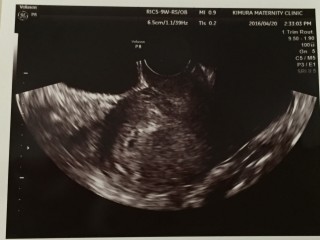

高温期20日目で、6.3㎜の胎嚢見れました! AIH6回目、2年でようやくです。 何度か妊娠しましたが(出産も含め)、やはり成長はその時で違いました。 また2週間後健診です!